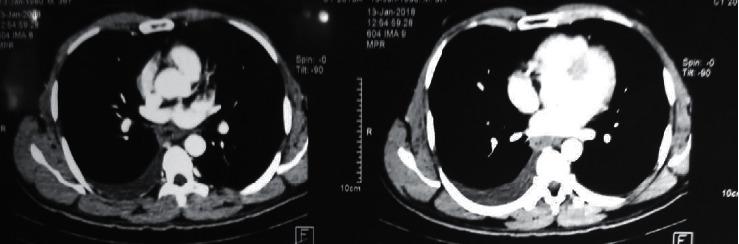

Eosinophilic gastroenteritis (EGE) is an uncommon disease characterized by eosinophilic infiltration of the digestive tract, which occurs due to an uncertain aetiology. Although autoimmune diseases can later present as EGE, it is unusual for EGE to have positive autoimmune antibodies without the presence of an overt autoimmune disease. We report a 38-year-old previously healthy man who presented with abdominal discomfort and loose stools with pleural and peritoneal effusions progressing over several weeks. His investigations revealed severe eosinophilia in peripheral blood and ascitic fluid, and a laparoscopic full-thickness biopsy from the ileum demonstrated infiltration of eosinophils in all three layers of the intestine. There were no clinical features or investigations suggestive of parasitic disease, other diseases associated with eosinophilia, or autoimmune disease. Further investigations showed a highly positive ANA, positive p-ANCA, but did not meet the criteria to diagnose a specific autoimmune disease. The eosinophilia responded to an elimination diet with gradual resolution of eosinophilia and effusions, and once it reappeared after introduction of a normal diet.

嗜酸性粒细胞性胃肠炎(EGE)是一种罕见疾病,其特征为消化道嗜酸性粒细胞浸润,病因不明。虽然自身免疫性疾病后期可表现为EGE,但EGE在无明显自身免疫性疾病的情况下出现自身免疫抗体阳性并不常见。我们报告一名38岁既往健康男性,他出现腹部不适和腹泻,伴有胸腔和腹腔积液,病程持续数周。他的检查显示外周血和腹水严重嗜酸性粒细胞增多,回肠腹腔镜全层活检显示肠道三层均有嗜酸性粒细胞浸润。没有临床特征或检查提示寄生虫病、其他与嗜酸性粒细胞增多相关的疾病或自身免疫性疾病。进一步检查显示抗核抗体(ANA)高度阳性、核周型抗中性粒细胞胞浆抗体(p-ANCA)阳性,但不符合诊断特定自身免疫性疾病 的标准。嗜酸性粒细胞增多对排除饮食有反应,嗜酸性粒细胞增多和积液逐渐消退,恢复正常饮食后嗜酸性粒细胞增多再次出现。